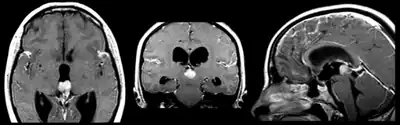

| Pineoblastoma localized predominantly in posterior part of the third ventricle | |

Pineoblastoma is a malignant tumor of the pineal gland. A pineoblastoma is a supratentorial midline primitive neuroectodermal tumor.[1][2]